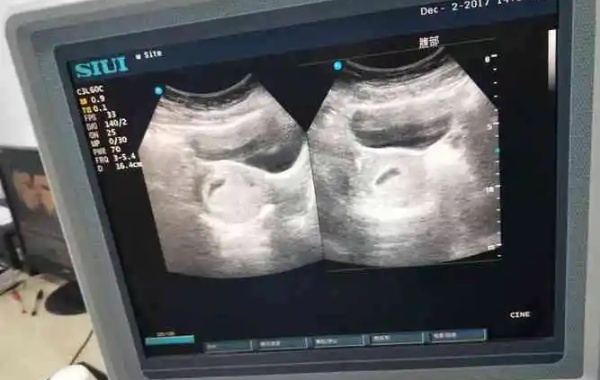

孕囊形状看男宝女宝很准不是真的。因为女性在怀孕早期孕囊的形状也是比较多样的,做b超的时候医生截面会截取的方位不一样,有的横截面,有的截取竖截面,通过孕囊形状并不能判断男宝女宝,而且孕囊的形状由其张力和含氧量决定,会自行改变,怀孕天数不同看到的孕囊也可能不一样。医学上对孕囊的大小和形状进行检测,主要是判断胚胎的发育是否健康,还可以根据孕囊的大小,推算出孕龄的长短,孕囊基本上都是三维的球形或者椭圆体,